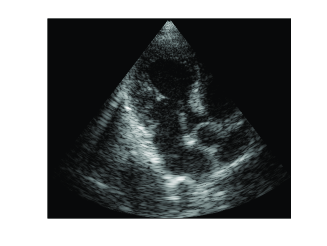

The resulting images, corresponding to two different frames, are shown in Figs. 7f (b) and (e). Although the images are not identical to those obtained by standard beamforming (Figs. 7f (a) and (d)), it can be easily seen that optimization, based on the assumption that the signal of interest is compressible, allows to reconstruct both strong reflectors and speckle. Table II reports corresponding values of NRMSE and SSIM. Although the quantitative values are reduced compared to those obtained in Sec. IV-B, important information, e.g. the thickness of the heart wall and the valves, as well as the speckle pattern, essential for tracking tools, are preserved.

To compare the proposed method with the previously developed optimization based approach, we solved (29) with OMP, while assuming strong reflectors in each direction . Resulting images, shown in Figs. 7f(c) and (f), depict the strong reflectors, observed in Fig. 7f(a) and (b), while the speckle is completely lost, degrading the overall image.

Using this set, beamforming in frequency was performed according to (16) and (20), yielding the DFT coefficients of the beamformed signal. In this setup the sampling rate remained unchanged, but frequency domain beamforming was performed at a low rate. In our experiments we computed DFT coefficients of the beamformed signal, using DFT coefficients of each one of the detected signals. This corresponds to real-valued samples used for beamforming in frequency. The number of samples required by demodulated processing rate is . Hence, beamforming in frequency is performed at a rate corresponding to of the demodulated processing rate. Images obtained by low-rate beamforming in frequency and standard time-domain beamforming are presented in Fig. 11. As can be readily seen, we are able to retain sufficient image quality despite the significant reduction in processing rate.

(a)

(b)